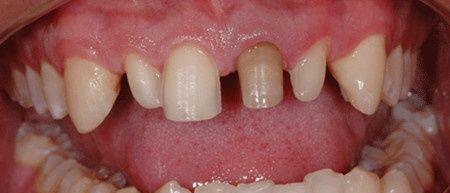

還很年輕,不知道為什么牙齒一個(gè)接著一個(gè)的掉,牙齒問(wèn)題實(shí)在是讓人很無(wú)奈,想修復(fù)牙齒,了解到有很多種方法可以修復(fù)甚至是“再生”。但是問(wèn)題來(lái)了,到底那種方法好?那種修復(fù)方式好呢?其中,烤瓷牙跟種植牙又有何區(qū)別呢?

烤瓷牙做法:做烤瓷牙需要將缺牙兩邊的兩個(gè)牙齒磨小,然后再在上面套上牙冠,修復(fù)完后的牙齒,需要依靠鄰近的好牙才能進(jìn)行咀嚼等動(dòng)作。大的缺點(diǎn)就是對(duì)真牙傷害太大(把健康的牙齒磨小)。